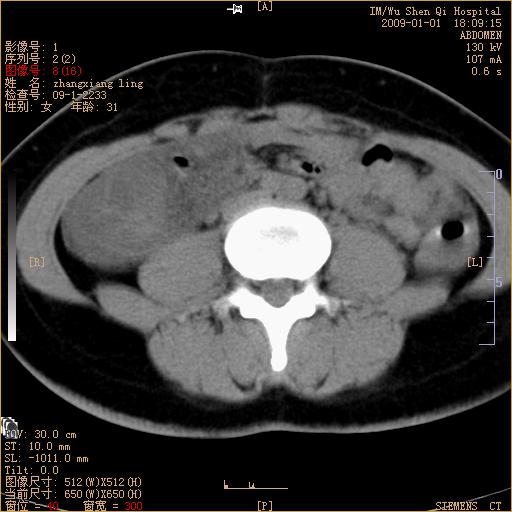

标题: CT17527:F31Y,腹痛伴血便9小时 [打印本页]

标题: CT17527:F31Y,腹痛伴血便9小时

升结肠肠壁不规则增厚,肠腔狭窄,考虑升结肠占位,建议增强扫描

升结肠肠壁不规则增厚,肠腔狭窄,考虑升结肠占位,建议增强扫描,不除外肠套叠.

升结肠肠壁不规则增厚,似呈同心圆改变,其有积液。结合病史首先考虑肠套叠伴肠壁坏死可能性大,结肠肿瘤待排。

患者已手术,结果肠系膜血栓形成肠坏死

结果:患者已手术,结果肠系膜血栓形成肠坏死。回过头再看局部肠壁增厚有分层(高密度坏死及低密度水肿)表现。